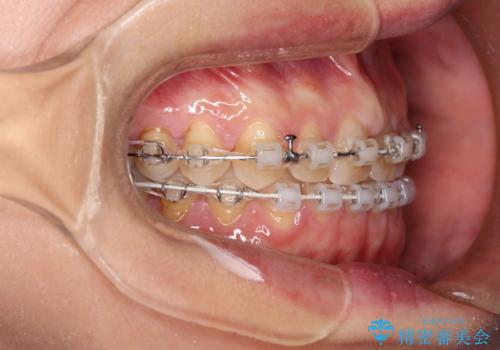

【審美装置】すきっ歯をワイヤー装置で治したい

- 審美装置

- 前歯のすきっ歯が気になるということで来院されました。今回は抜歯はしないためワイヤー矯正かインビザライン矯正のどちらでも治療可能でしたが、患者さまのご希望により表のワイヤー装置にて治療をおこないました。

前歯に隙間がいくつかあったため、今回は上下でゴムかけを行いスペースを埋めるための力をかけて閉じました。もう少し早く終了する予定でしたが、ブラッシング不良による歯肉腫脹があり、一部スペースクローズに時間がかかりました。